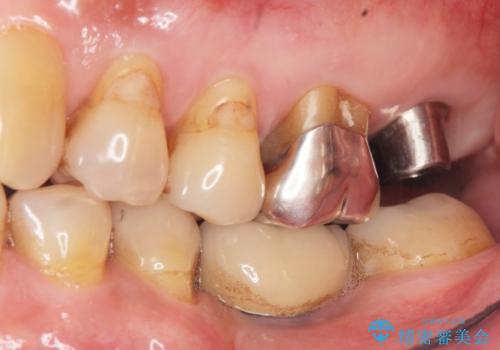

奥歯でしっかりと咬むことができるようになり、ご満足頂けました。

初診時から治療終了時までのレントゲンをお見せして説明差し上げたところ、「お~!骨ができている!」と喜んで下さいました。

インプラントの種類:ストローマン BLT

クラウンの種類:メタルボンドクラウン エコノミー